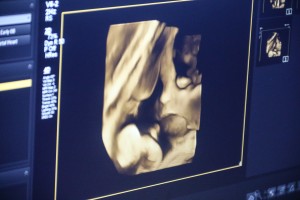

Dispanzer za žene dobio najsavremeniji ultrazvučni aparatOvo je visokosofisticirani aparat koji ima četiri sonde, od kojih je jedna sonda 3D/4D i omogućava jedan izuzetno lep prikaz fetusa i ploda. Verujem da će trudnice biti izuzetno zadovoljne i srećne što će imati priliku da vide svoju bebu u takvoj tehnologiji ovde kod nas, u Domu zravlja - objašnjava dr Tatjana Popović, specijalista ginekologije i akušerstva, načelnik Službe za zdravstvenu zaštitu žena i dece u Domu zdravlja.

Novi 4D ultrazvuk na odeljenu ginekologije u Dispanzeru za žene Novi 4D ultrazvuk na odeljenu ginekologije u Dispanzeru za žene Novi 4D ultrazvuk na odeljenu ginekologije u Dispanzeru za žene Novi 4D ultrazvuk na odeljenu ginekologije u Dispanzeru za žene Novi 4D ultrazvuk na odeljenu ginekologije u Dispanzeru za žene Novi 4D ultrazvuk na odeljenu ginekologije u Dispanzeru za žene Novi 4D ultrazvuk na odeljenu ginekologije u Dispanzeru za žene Novi 4D ultrazvuk na odeljenu ginekologije u Dispanzeru za žene